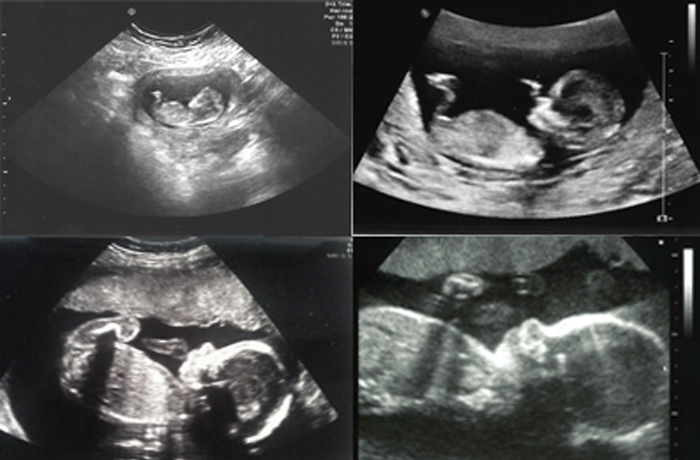

Кардиологическое УЗ-исследование сердца плода

УЗИ сердца плода

На такое УЗИ специалист направляет с 19-й по 21-ю неделю беременности. Его необходимо провести, чтобы убедиться в нормальной работе сердца ребенка. Бесперебойное сокращение сердечной мышцы говорит о нормальном развитии плода.

Сердцебиение плода регистрируется уже примерно в 6 акушерских недель. А вот оценить структуру сердца можно уже во втором триместре, в рамках 2 скрининга или с помощью самостоятельной процедуры УЗИ сердца плода. ЭХО КГ позволяет обнаружить следующие врожденные пороки сердца:

Важно понимать, что не все пороки сердца можно выявить в рамках этого метода диагностики, например, открытое овальное окно обнаруживают уже после рождения малыша. Однако многие аномалии удается обнаружить заранее, еще до рождения, что позволяет правильно подготовиться к послеродовому периоду — запланировать необходимое вмешательство.